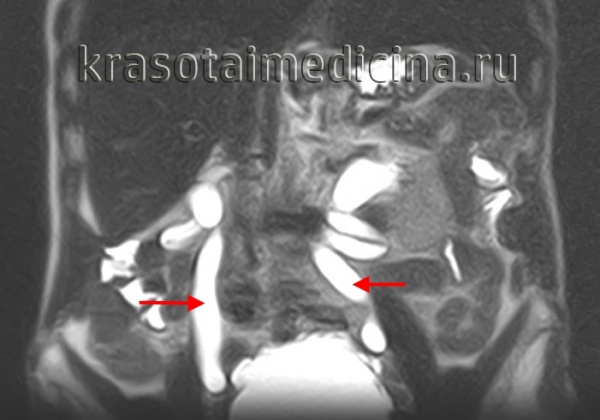

• Инструментальные методы. УЗИ почек, мочевого пузыря, ТРУЗ с контролем остаточной мочи являются основными диагностическими методами, направленными на выявление причин возникновения гидроуретанов. Экскреторная урография не проводится при хронической почечной недостаточности. После получения смешанных результатов проводится КТ и МРТ. Эти процедуры предпочтительны для определения опухоли забрюшинного пространства, сдавливающей мочеточник; нет никакой разницы с увеличением креатинина. По показаниям проводится ренография, уретеропиелоскопия, нисходящая цистография, КУД.

ИРП ОБП и забрюшинное пространство. Выраженное стойкое расширение мочеточников с обеих сторон.